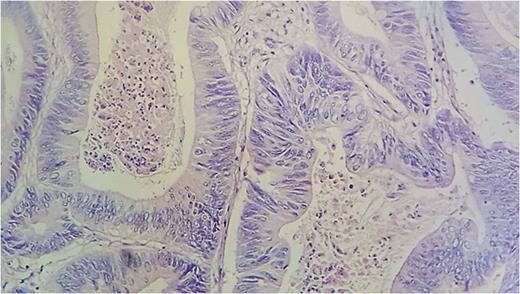

A 59-year-old wowan was referred for intestinal occlusion for 2 days. She had a history of appendicectomy. The computed tomography (CT)-scan found an obstructed colon, above a wall-thickening of the sigmoid colon. A colonoscopy was performed and showed an ulcerated and budding tumor located in the sigmoid colon, and an ulcerated stenosis in the coecum. But, after the colonoscopy, the patient presented with abdominal pain and tenderness, consistent with peritonitis due to perforation of the tumor; she underwent emergency ileostomy. After that, ileocolectomy has been performed. Histopathological examination of the specimen revealed a well-differentiad adenocarcinoma of the sigmoid, perforating the serosa (pT4), with perineural invasion. The margins were negative, two lymph nodes of the 12, were invaded by the tumor. Therefore, the tumor was classified, stage IIIC (pT4bN1b, AJCC 2009). The patient has been discharged from hospital and adjuvant chemotherapy (Capecitabine) was prescribed for her. The laparascopic reversal has been performed few months later. Three years later, a CT-scan performed during a follow-up found two nodules in the spleen, the first was located in the superior pole measuring 37 × 32 mm2 ; the other nodule was located in the middle part of the spleen, and measured 22 × 18 mm2 ; there was no other suspected location. Splenectomy for metastastatic colon cancer has been decided. The resected spleen measured 15 × 9 × 3 cm3, with two round subcapsular whitish tumors, respectively in the upper pole and in the hilum, 6 × 6 × 4 cm3 and 3 × 3 × 2 cm3 in dimension (Fig. 1). The histological examination found that these nodules are metastasis from a well-differentiated adenocarcinoma of the colon, without any capsular invasion. The tumor was composed of large glands lined by irregular columnar cells with eosinophilic abondant cytoplasm. Large focis of necrosis in the lumen of the tumoral glands were seen (Figs 2 and 3). The patient recovered well after surgery, and a pseudo-adjuvant chemotherapy (secondary adjuvant chemotherapy) was decided after multidisciplinary meeting.

Histological aspect of the tumor showing a glandular pattern with large focis of necrosis (HES×10).

High power view of the tumoral glands lined by columnar cells with abundant eosinophilic cytoplasm and irregular nucleis (HES×40).